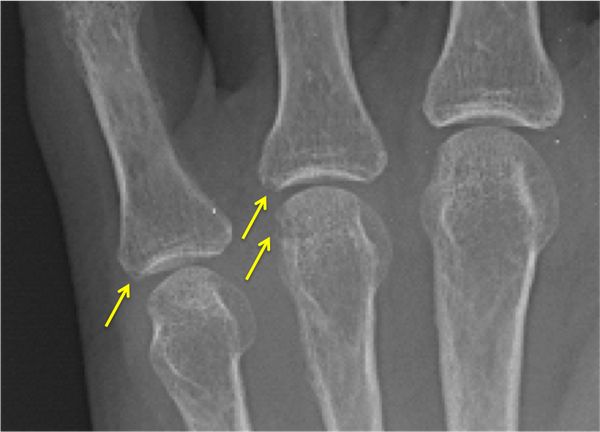

При использовании методов визуализации, таких как ультразвуковое исследование суставов (УЗИ), рентген, компьютерная или магнитно-резонансная томография (КТ или МРТ), могут быть видны признаки дегенерации и разрушения хряща, остеопороза, эрозий суставных поверхностей костей, костных разрастаний, синовитов (воспаления синовиальной оболочки) и поражения сухожильно-связочного аппарата. Для некоторых заболеваний характерна типичная рентгенологическая картина, например изменения по типу «карандаш в стакане» при мутилирующем псориатическом артрите.

![Эрозии суставных поверхностей костей [24] Эрозии суставных поверхностей костей [24]](/media/bolezny/poliartrit/erozii-sustavnyh-poverhnostyay-kostyay-24_s.jpeg?dummy=1766053881926)

Эрозии суставных поверхностей костей [24]